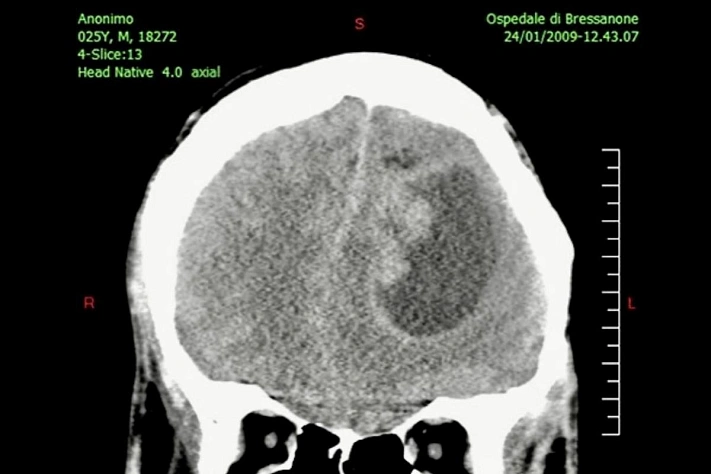

Команда израильских исследователей представила экспериментальный метод лечения опухолей мозга, который помогает лекарствам проходить через гематоэнцефалический барьер — естественную «броню» нашего мозга. Если подход подтвердит эффективность, у врачей появится новый инструмент против одной из самых опасных и плохо поддающихся терапии форм рака.

Опухоли мозга остаются одной из самых сложных областей онкологии. Даже когда врачи знают, какие препараты способны замедлить рост раковых клеток, их действие ограничено: мозг защищён плотной сетью капилляров, которые не пропускают большую часть веществ. Этот механизм спасает нас от токсинов и инфекций, но одновременно делает опухоли практически недоступными для лечения.

Если метод подтвердится в клинических испытаниях, он может стать значимым дополнением к существующим стратегиям лечения. Прежде всего — к терапии глиобластомы, одного из самых агрессивных типов опухолей. Сейчас пациенты проходят операцию, лучевую терапию и химиотерапию, но даже при комплексном подходе болезнь часто возвращается.